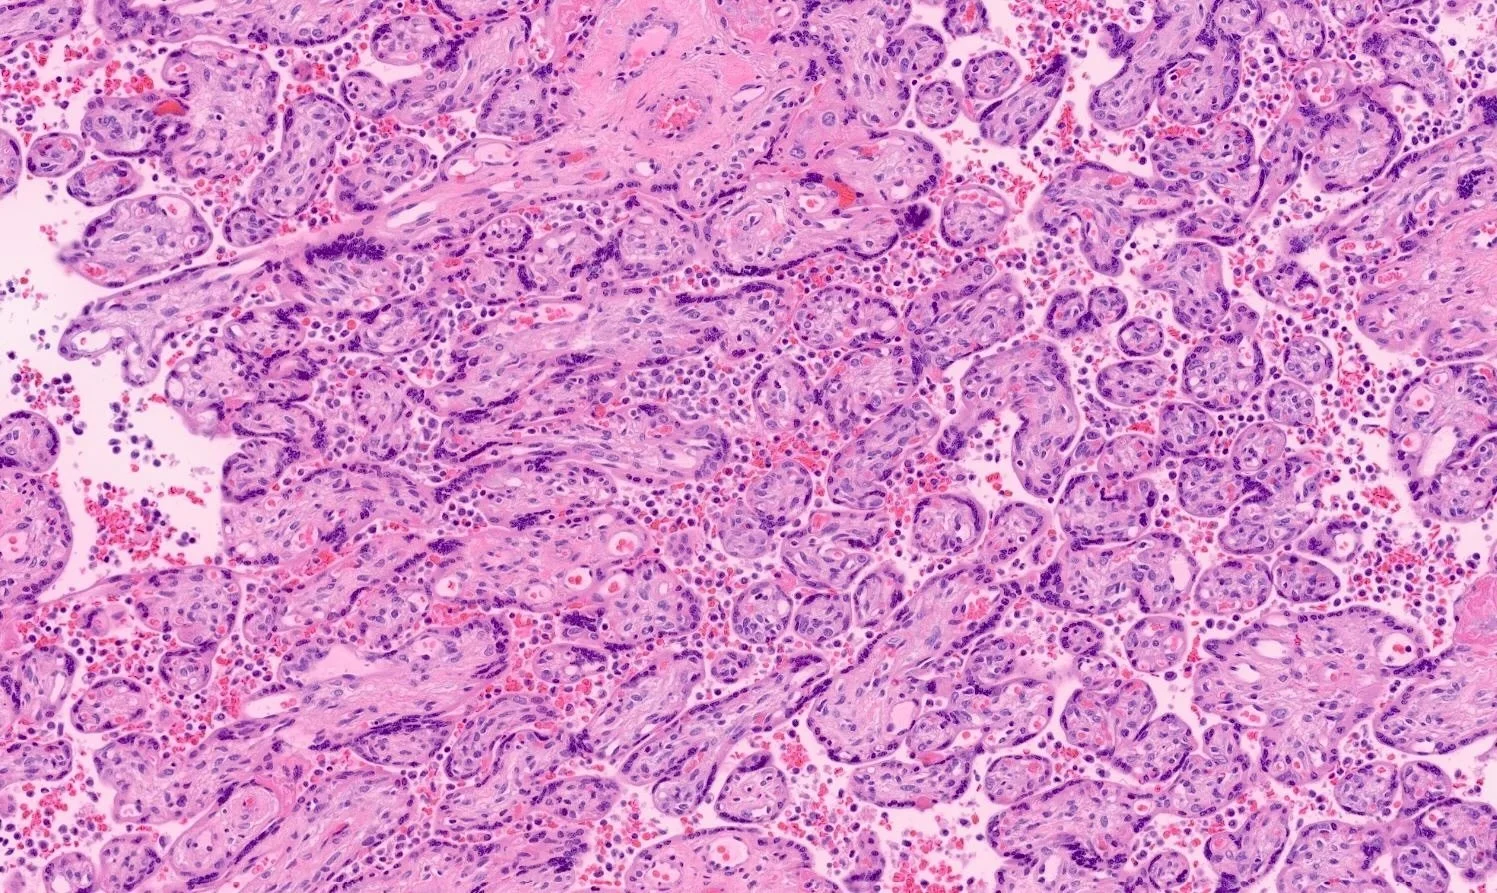

The four most common patterns of abnormal placentation/placental injury are:

1. Maternal vascular malperfusion

2. Foetal vascular malperfusion

Examples of abnormal immune placentation